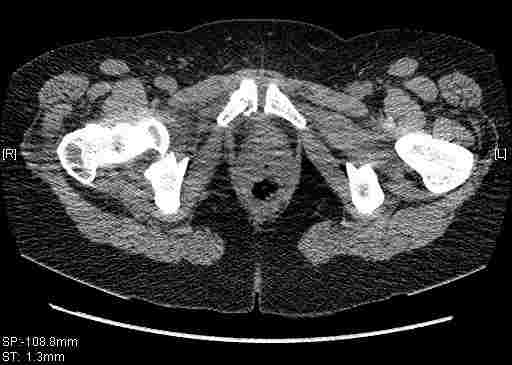

Удалось сегодня вывести пациентку в соседнюю больницу, где есть кт. Срезы сделаны только горизонтальные.

Следом 3d

Приветствую,Антон.Рункова рядом нет,но после полученных данных КТ,обсуждали совместно.Итог обсуждения-развернутый ответ дать не получится,т.к.срезы выбраны не информативные.Если ориентироваться на данные 3D,то ,ИМХО,можно лечить на вытяжении.